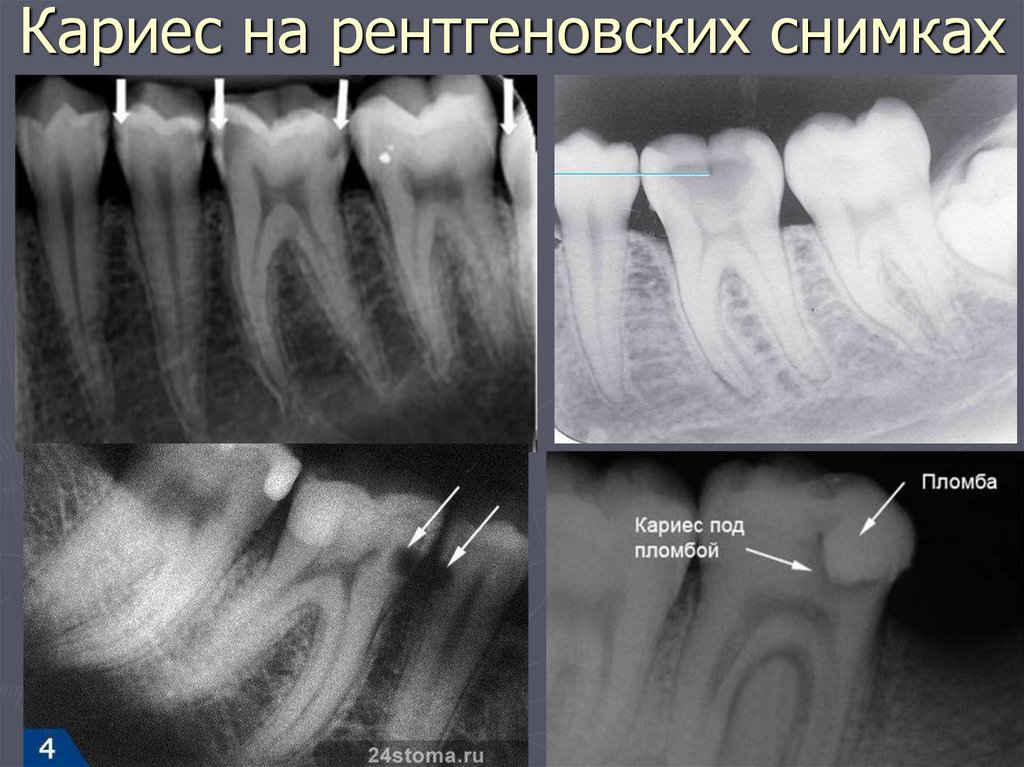

93. Кариес на рентгеновских снимках

94. Рентгенологическая классификация кариеса

РЕНТГЕНОЛОГИЧЕСКИЙ МЕТОД –

применяется:

в случаях крайнего затруднения

диагностики,

► при локализации полостей на

апроксимальных поверхностях,

► при тесном положении зубов.